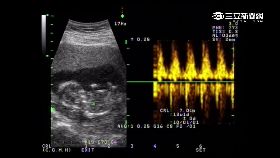

19歲女生雙胞胎 孩子爸竟有兩個人

同時生下的一對雙胞胎,孩子的爸竟不一樣?年僅19歲的...

19歲處女沒愛愛 一查竟懷孕5禮拜

沒愛愛也懷孕!美國麻薩諸塞州1名女子19歲時發現月經...